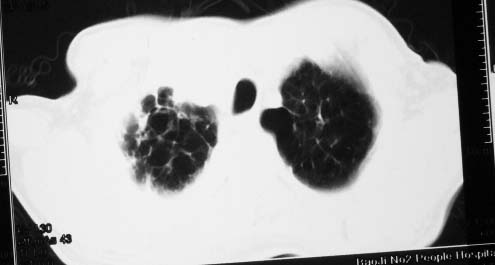

影象表现:右肺上叶大片状、网格状及索条致密影,蜂窝影,其内参杂斑点状小结节,密度不均匀,内见含气支气管像,纵隔内见肿大淋巴结.

影象表现:右肺上叶大片状、网格状及索条致密影,蜂窝影,其内参杂斑点状小结节,密度不均匀,内见枯枝样含气支气管像,纵隔内见肿大淋巴结.胸膜广泛增厚,前胸壁似受累.少量胸腔积液.纵隔内淋巴结的直径>1.5cm.右侧胸廓体积缩小.考虑:1 肺结核合并间质纤维化 2 细支气管肺泡癌

右肺上叶大片状、网格状及索条致密影,蜂窝影,其内参杂斑点状小结节,密度不均匀,内见枯枝样含气支气管像,纵隔内见肿大淋巴结.胸膜广泛增厚,前胸壁受累增厚.少量胸腔积液.纵隔内淋巴结的直径>1.5cm.右侧胸廓体积缩小.考虑: 细支气管肺泡癌并肺内癌性淋巴管炎。